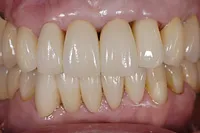

■治療前:上下顎 義歯での食事に満足されていない

■治療後:上下顎 複数本のインプラントを使い固定式で治療

| 主訴 | 現在義歯を使用しているが、しっかりと咬んでなんでもおいしく食事したい |

| 治療方法 | 上下顎 複数本のインプラントを使用しての治療 |

| 治療期間 | 約1年 |

| 通院回数等 | 約20回 |

| 費用 | 約600万円(税込) |

| リスク・副作用 | 術後の腫れ・痛み |